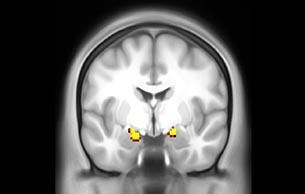

BOLD fMRI activation, depicted in color, of left anterior insula (MNI plane z = 8 mm) in a single subject by a contrast between viewing and matching faces with negative emotion (angry, sad, scared) versus happy faces. The voxelwise threshold is p < 0.001, and colored voxels survive false discovery rate correction to p < 0.05. The activated voxels in color are overlaid on the subject's own 3D-TFE image displayed in grayscale, after transforming the data to MNI space. The fMRI pulse sequence was a single shot FFE echo planar acquisition using MultiBand SENSE factor 6, dS SENSE factor 1, isotropic voxel size 2.4 mm, 60 transverse slices, TR 950 ms, TE 30 ms, flip angle 52 degrees, 517 dynamic scans, total scan duration 8:21 minutes. Image provided by James M. Bjork, PhD, Associate Professor of Psychiatry at VCU.